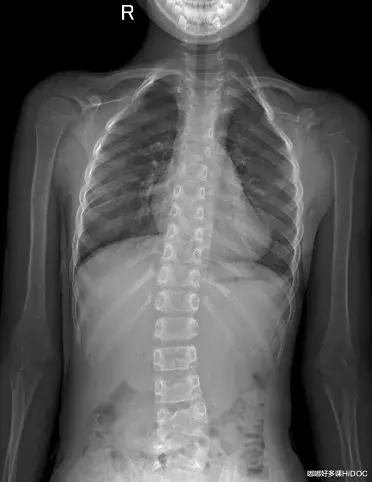

先天性脊柱侧弯站立、躯干前屈图。这例弯曲程度已比较大,一般孩子达不到这种程度,家长如有怀疑,可带孩子到医院拍片就诊。

三、影像学检查最为精准

自测方法存在一定的不准确性,若要精确,各位家长带孩子来医院骨科,做X线、CT、核磁共振(MRI)等影像学检查来观测孩子的确切情况。

以上两例的脊柱侧弯状况在X光片中已很明显,然而孩子外观的异常肉眼感受并不强烈。如果家长有这个担心,做个检查会更放心。